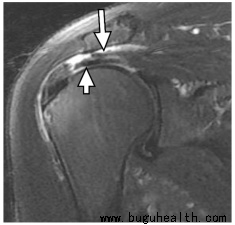

诊断肩袖损伤通常需要医生进行详细的身体检查和可能的影像学检查,如X光、MRI或超声波。常见的肩袖损伤包括肌腱炎、肌腱撕裂(部分撕裂或完全撕裂)以及肌腱退行性变。